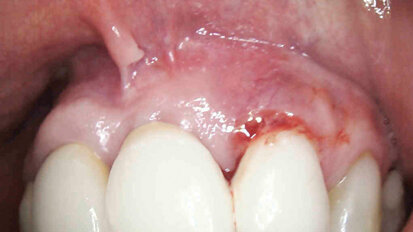

Efficace trattamento di un caso di perimplantite con laser Nd:YAG. Caso clinico

Il presente lavoro descrive la procedura con laser neodimio Nd:YAG 1064 nm per intervento di perimplantite.

Gestione di una monoedentulia in area estetica in presenza di esostosi vestibolare: caso clinico

La gestione del caso implantare in area estetica rappresenta una sfida per l’odontoiatria moderna. I pazienti sono sempre meno disposti ad accettare i...